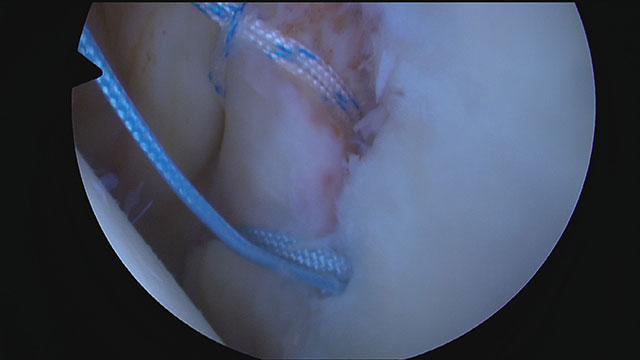

Nachdem Bohrlöcher in den vorderen Pfannenrand angelegt wurden, wird das Labrum mit Fäden angeschlungen und die Fäden mit speziellen Nahtankern in den zuvor angelegten Bohrlöchern fixiert.